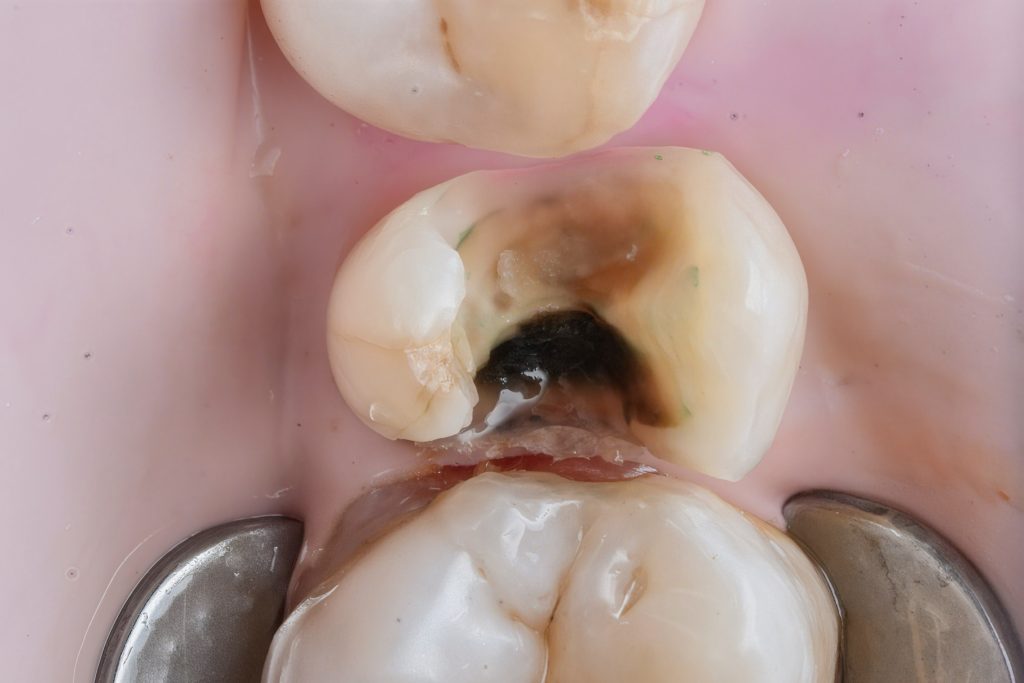

2. Caries Removal & Margin Management

Defective composite and caries were removed in a controlled manner preserving sound enamel walls. Teflon floss ties and wooden wedges used for separation and gingival retraction (Fig 3–6).

3. Matrix System Placement

Sectional matrix system used to recreate anatomical proximal walls. Ring stabilization applied to ensure tight contact and optimal emergence profile (Fig 7–8).

- Initial caries exposure and removal

- Proximal clearance and wedge placement

- Matrix placement and isolation refinement